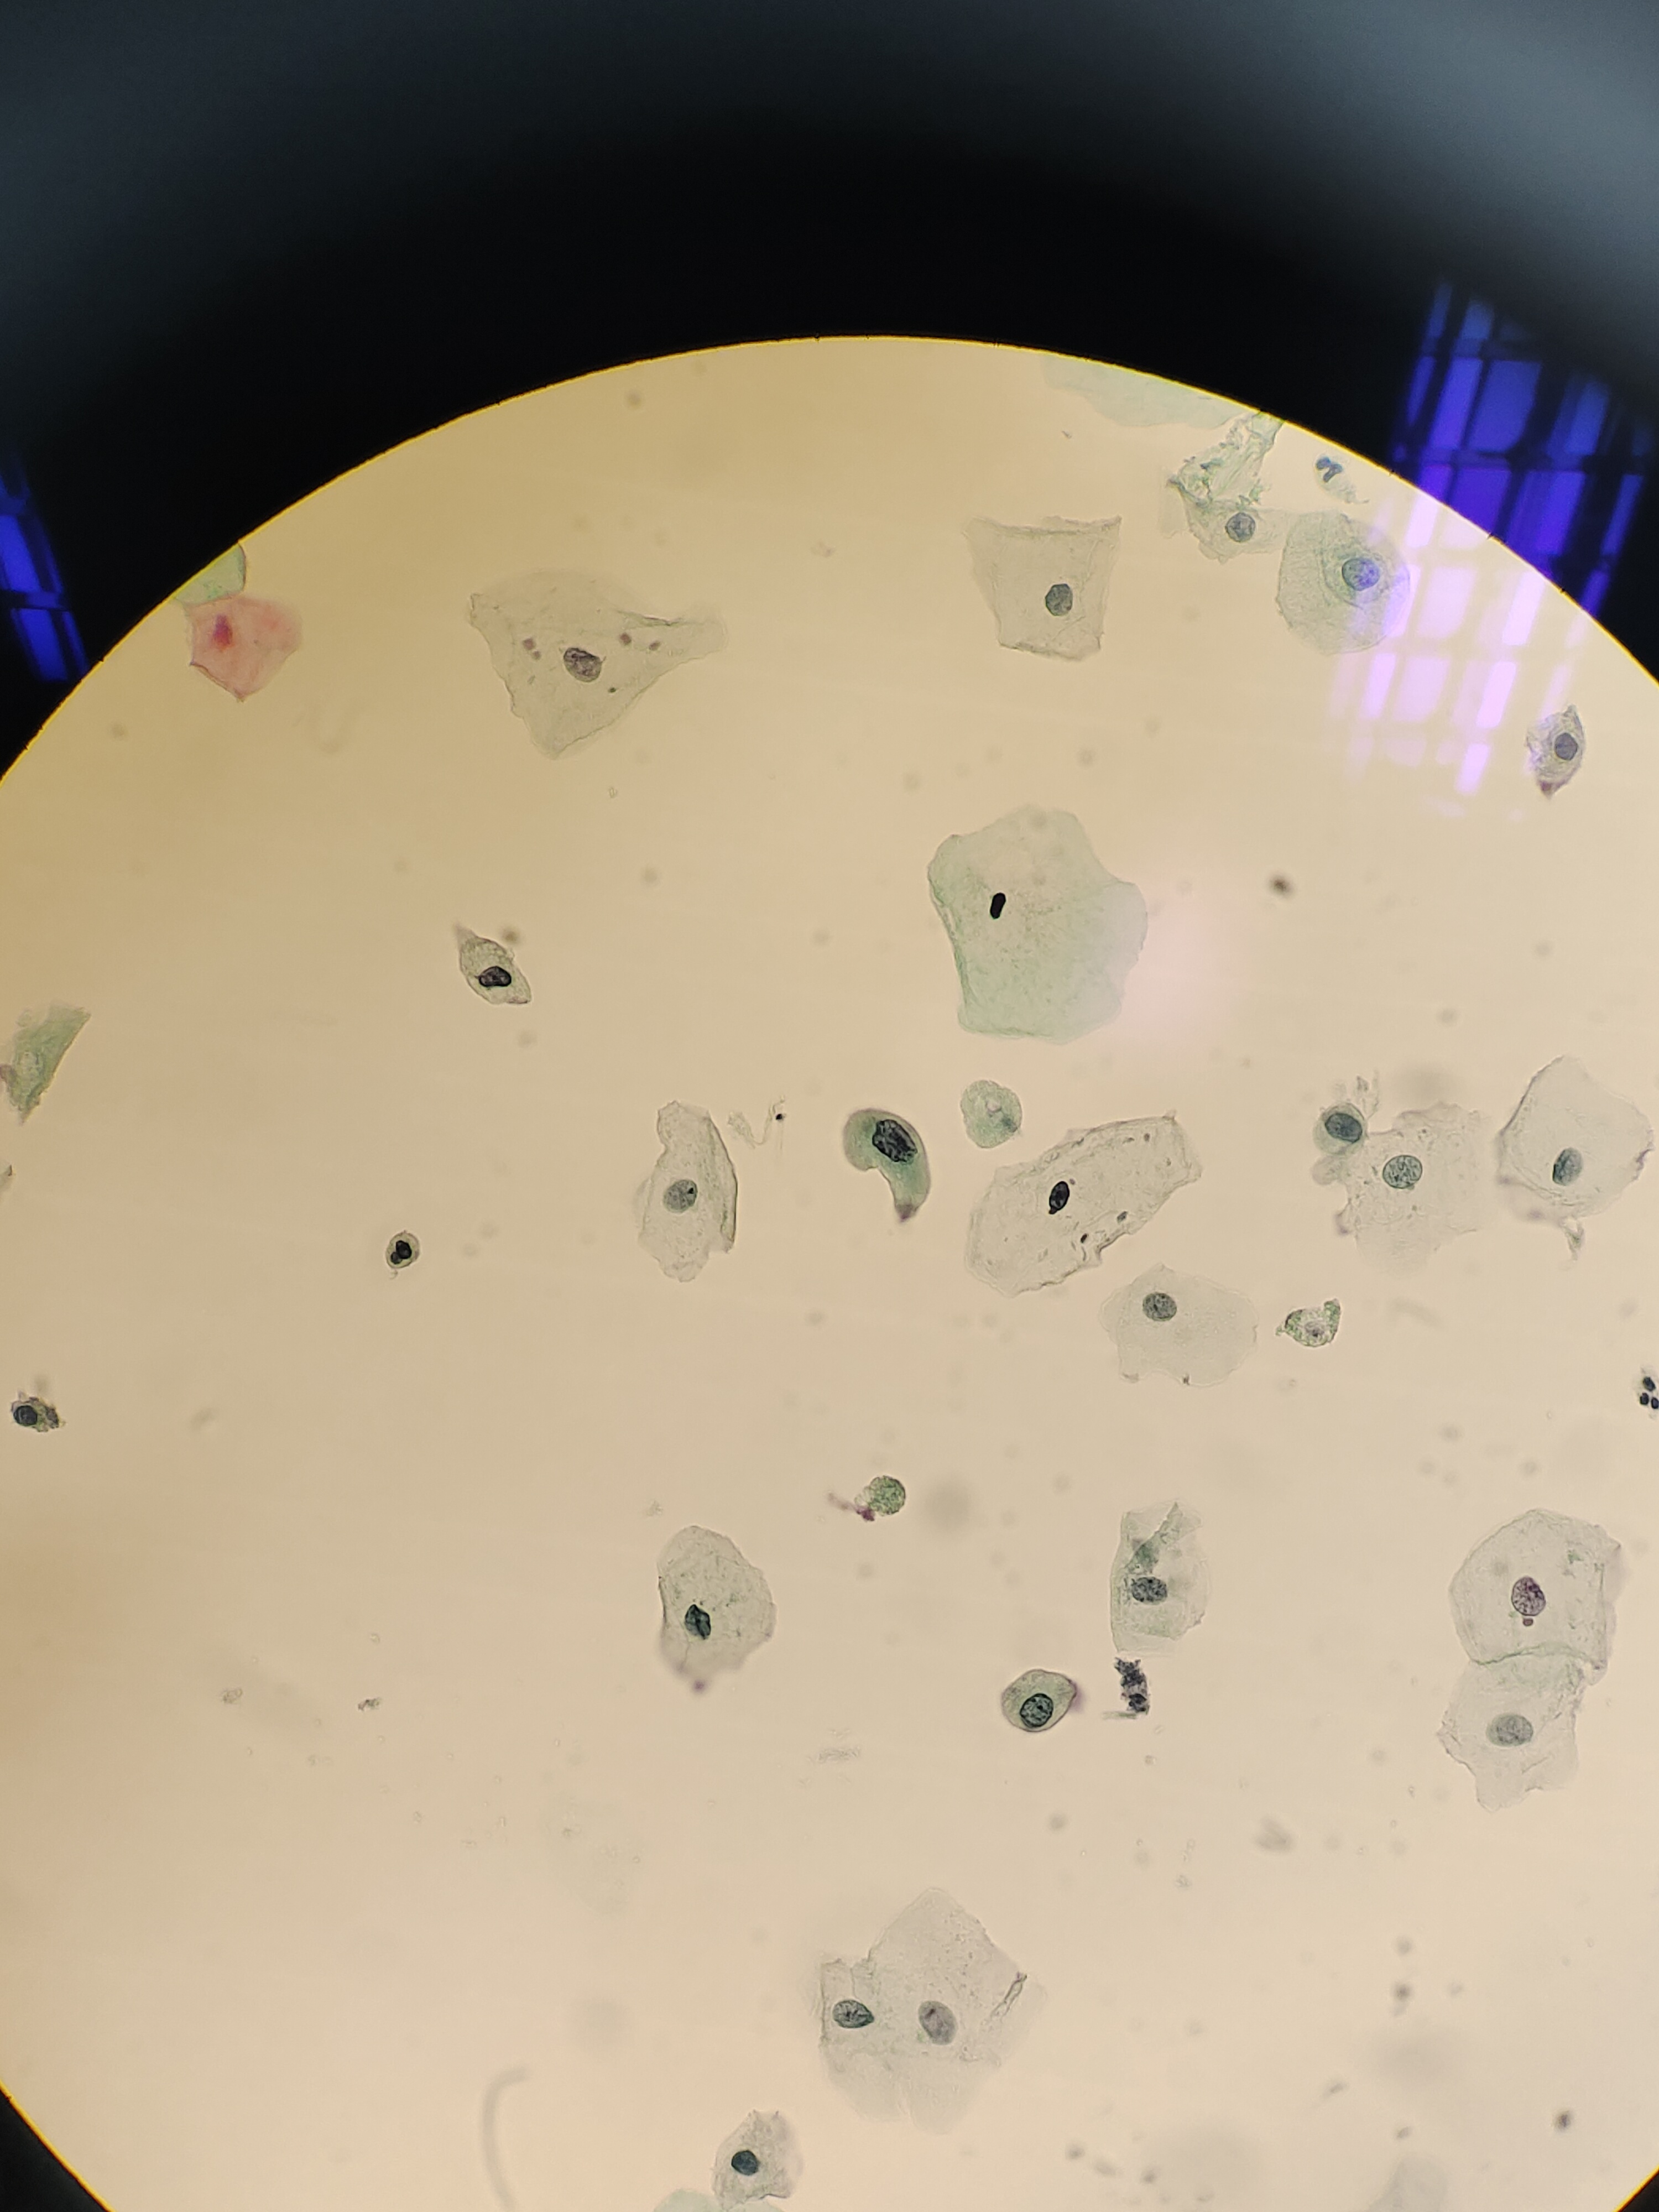

性别

女

年龄

65岁

一般病史

半年前血尿,服用抗生素2个月,后一直尿潜血阳性,右乳癌术后10余年,B超:双肾、输尿管,膀胱未见异常。老师们,有些核深染细胞,核异质细胞,轻度?

标本类型

尿

制片方法

液基

染色方法

未见肿瘤细胞。